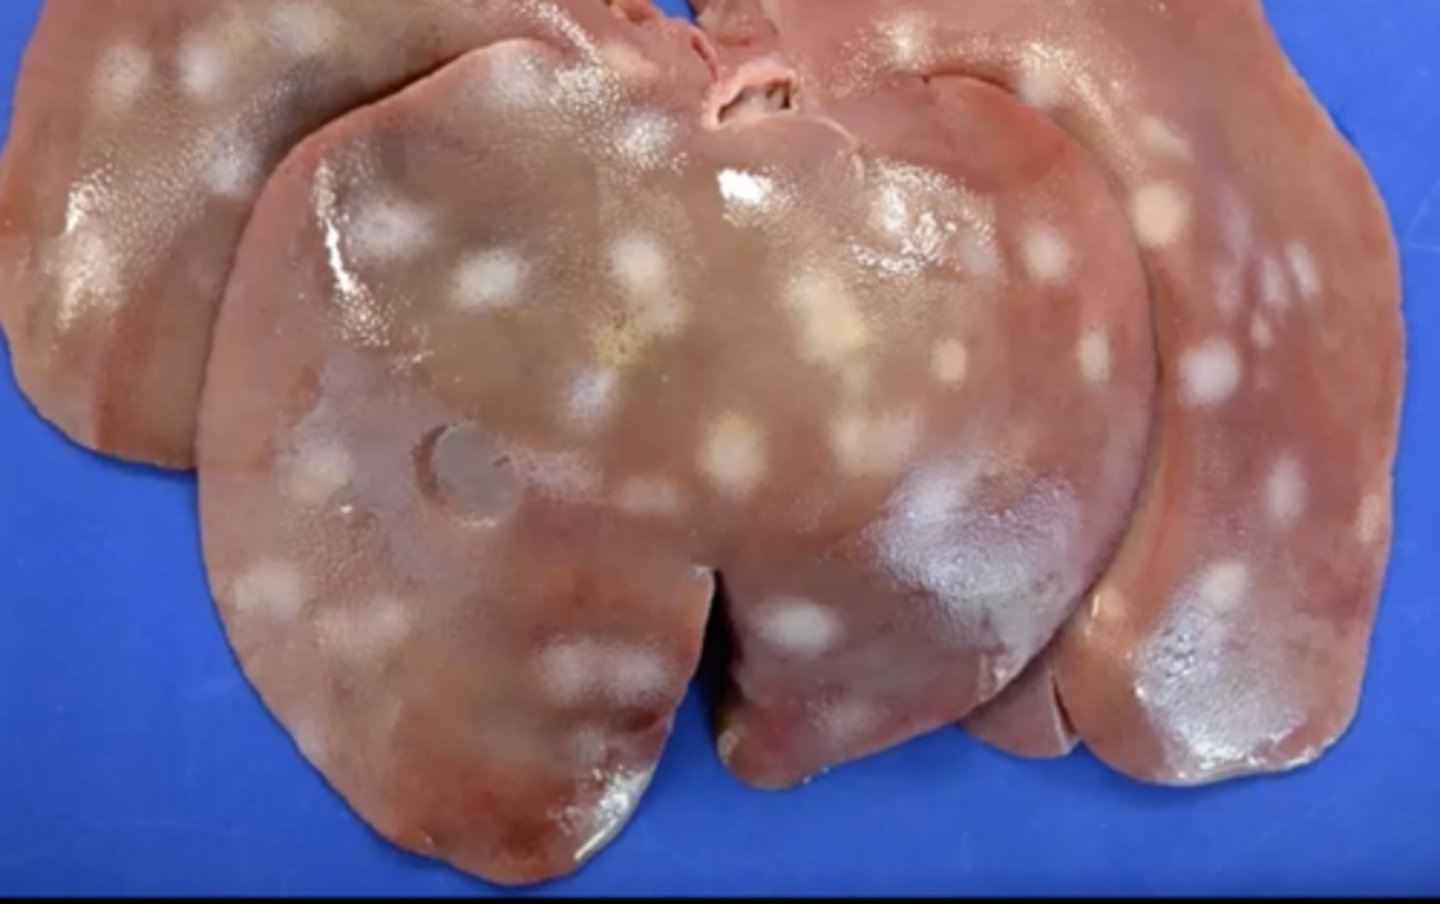

Milk spots - scars from ascaris suum migrating through the liver

Pig liver: What are these white sunken spots known as ?